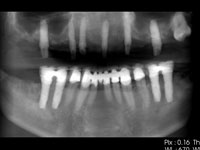

インプラント埋入後。

3Dレントゲン画像。

パノラマレントゲン画像。